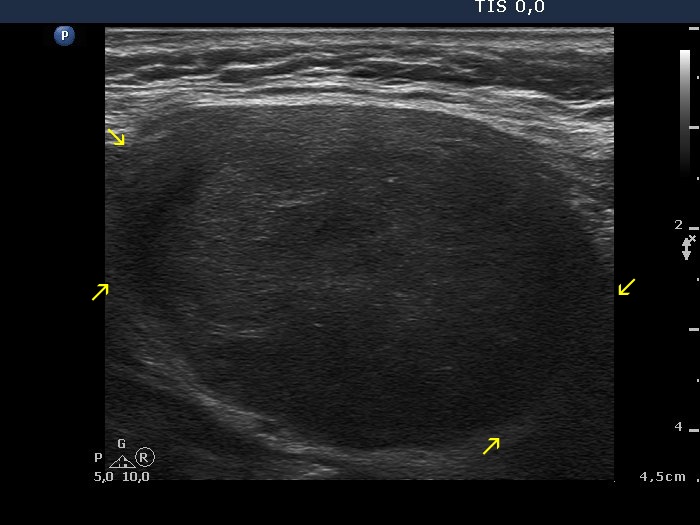

Lymph nodes - case conp 007 (ultrasonographic picture 2b)

Right lobe, longitudinal scan. The blur of the upper (left arrows) and the lower part (right arrows) of the nodule are very likely caused by the improper fitting of the probe to the neck of the patient.